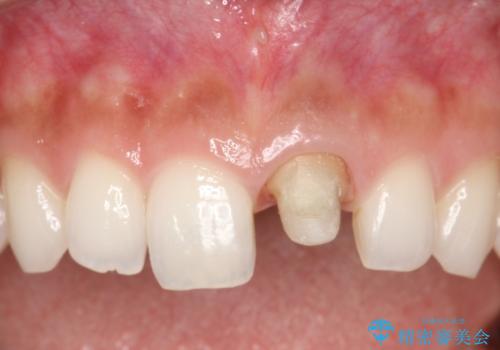

- 以前装着された前歯のかぶせ物の色を変えたいとのことで来院されました。

土台からの再治療を行い、オールセラミッククラウンを装着する治療計画としました。

- 天然歯を削ります